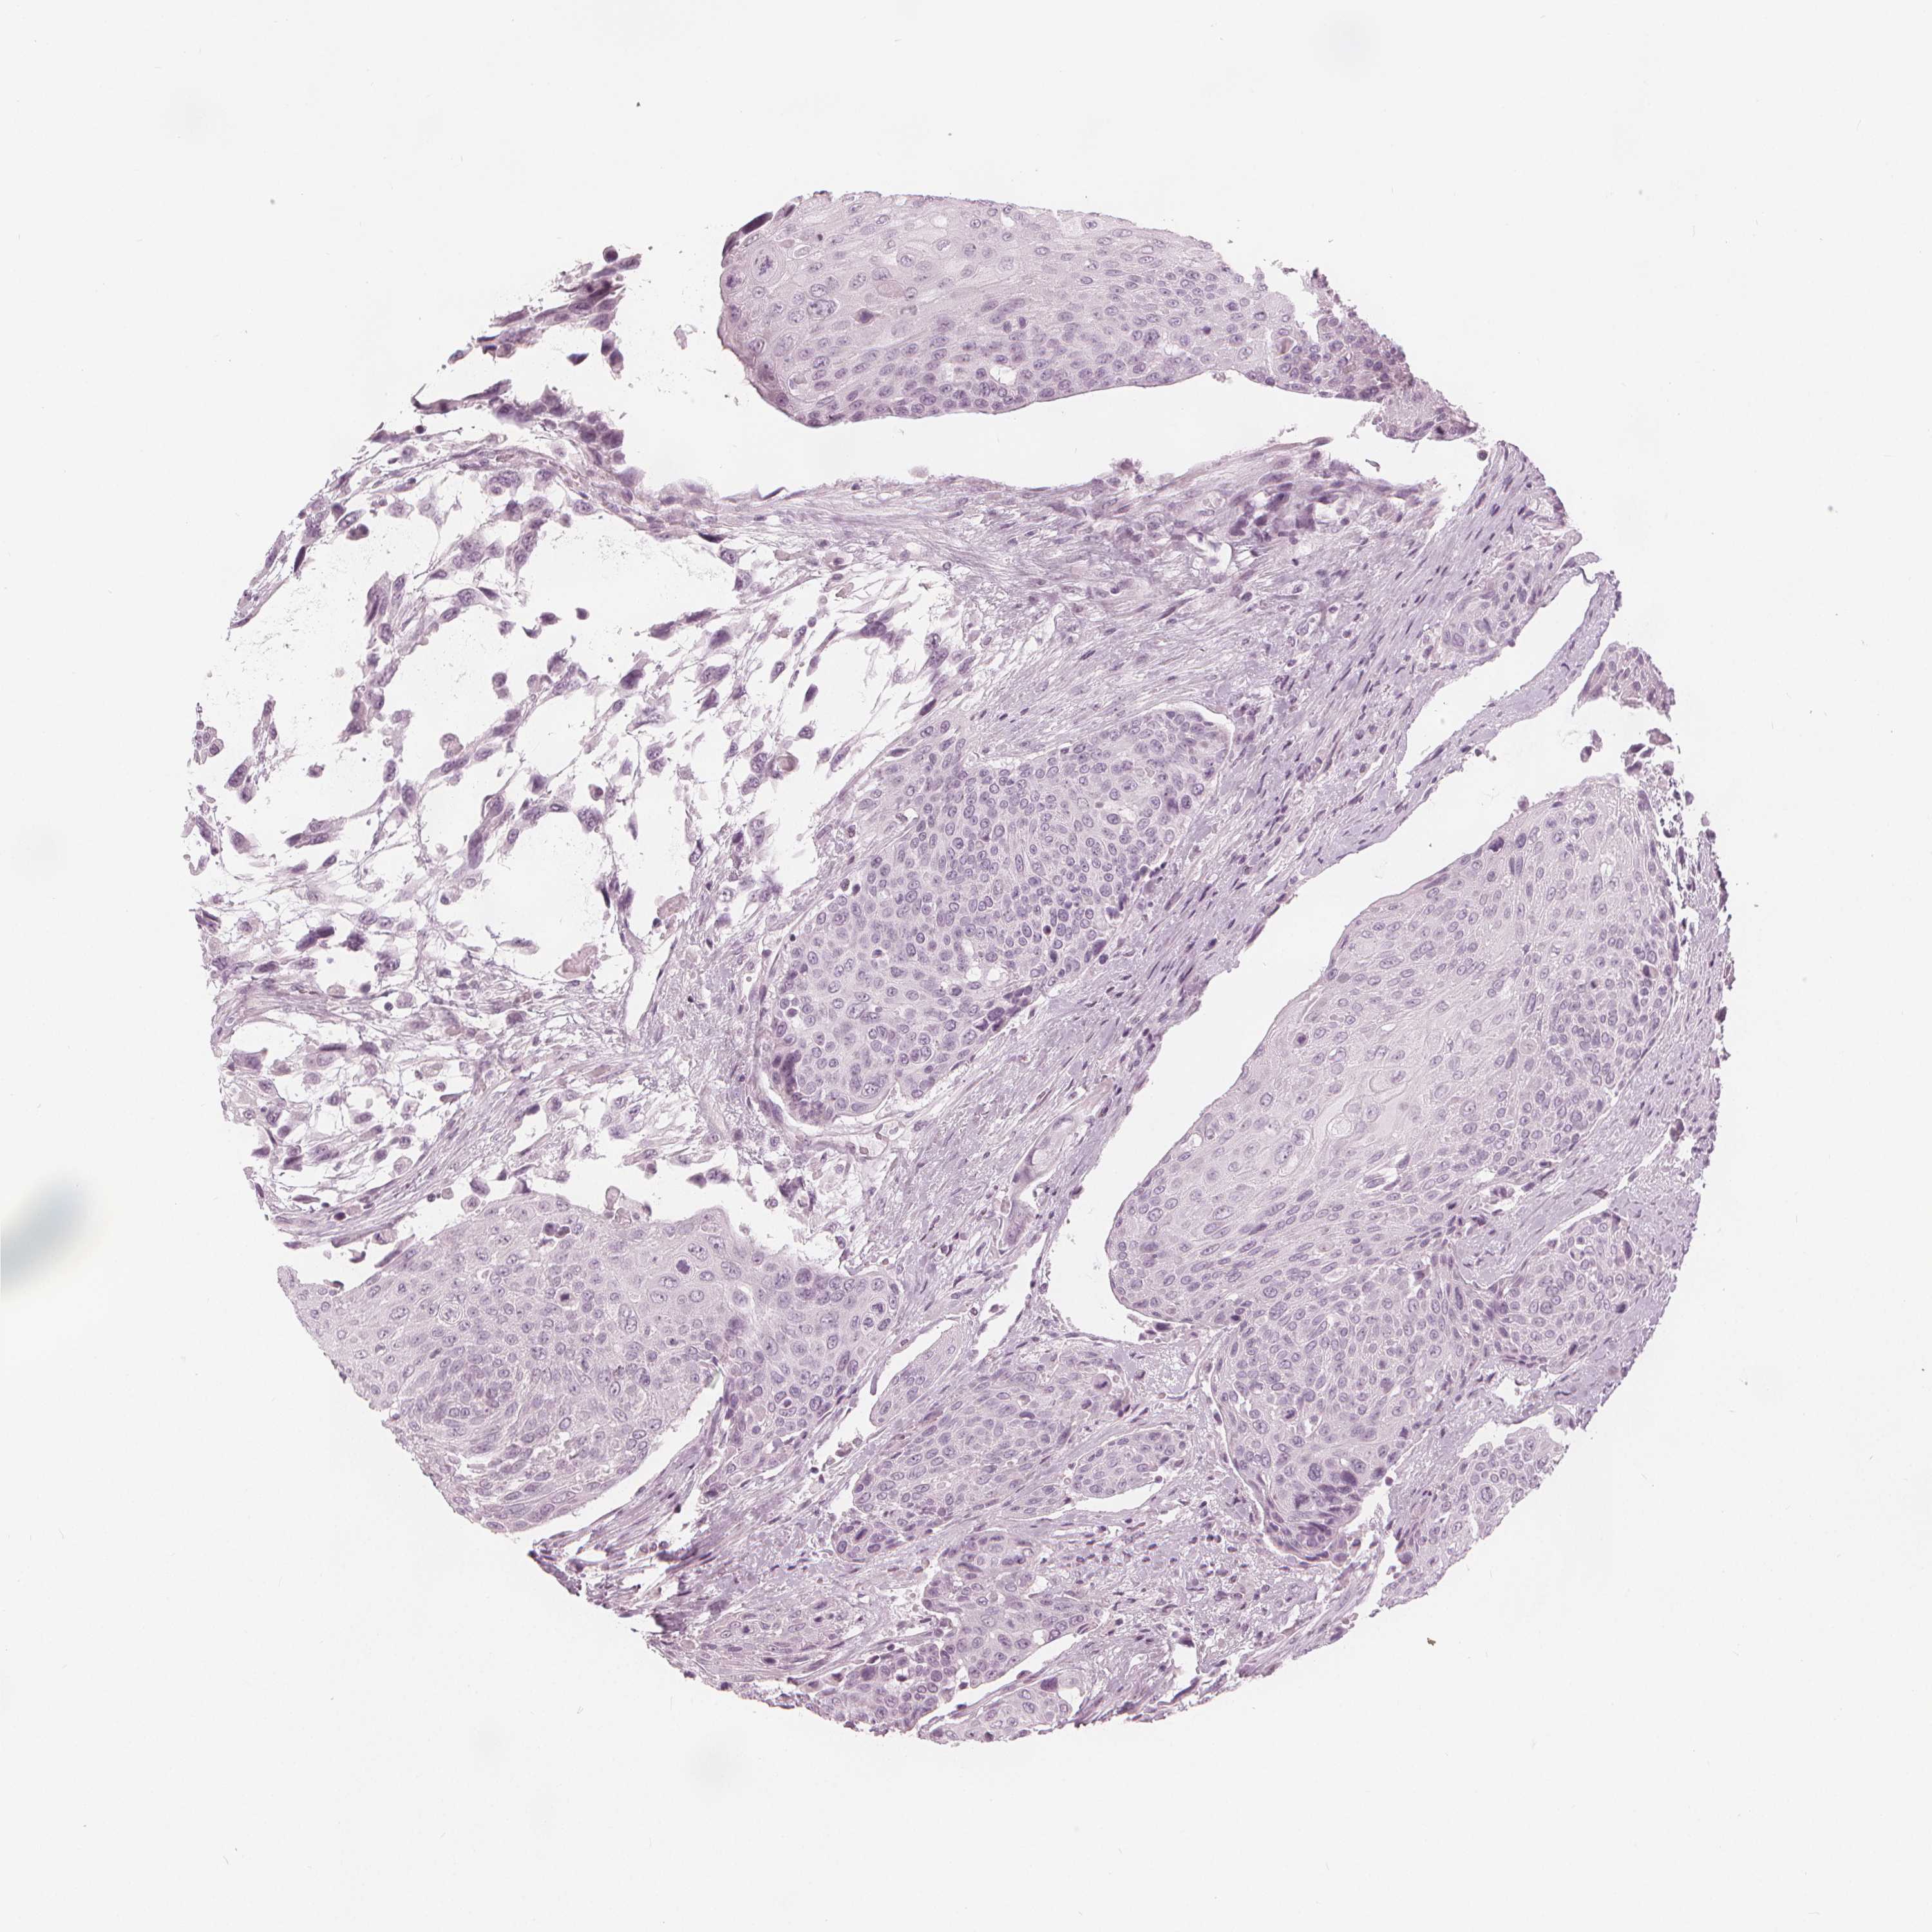

UROTHELIAL CANCER - Protein expressioni

A mouse-over function shows sample information and annotation data. Click on an image to view it in a full screen mode. Samples can be filtered based on level of antibody staining by selecting one or several of the following categories: high, medium, low and not detected. The assay and annotation is described here.

Note that samples used for immunohistochemistry by the Human Protein Atlas do not correspond to samples in the TCGA dataset.

Antibody stainingi

Antibody staining in the annotated cell types in the current human tissue is reported as not detected, low, medium, or high, based on conventional immunohistochemistry profiling in selected tissues. This score is based on the combination of the staining intensity and fraction of stained cells.

Each image is clickable and will lead to virtual microscopy that enables deeper exploration of all samples and also displays staining intensity scores, fraction scores and subcellular localization as well as patient and tissue information for each sample.

Antibody HPA020108

Antibody HPA029473

Antibody CAB016762

Urothelial carcinoma, High grade

Urothelial carcinoma, NOS

Urothelial carcinoma, Low grade